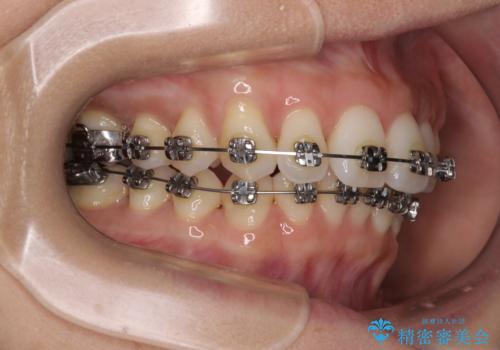

- 矯正装置

- メタルブラケット

- 前歯の突出感とデコボコを気にして来院された患者様です。

奥歯の噛み合わせをみると、上顎歯列が全体的に前突している状態であり、この咬み合わせのまま歯列を整えると出っ歯になってしまう可能性がありました。

アンカースクリューと補助装置を使用して上顎大臼歯を遠心移動させることで咬み合わせを改善し、ワイヤー装置によりデコボコを解消しながら口元の突出感も改善していくこととしました。

出っ歯になることなく、上下前歯が綺麗に接触する状態で仕上げることができました。